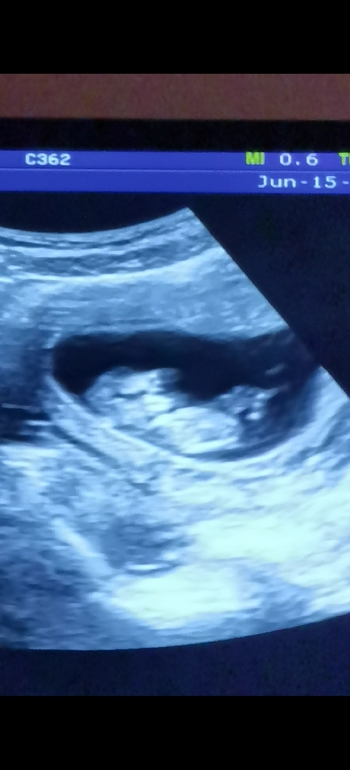

1 скрининг 😍 погадаем какого пола?)

Эмоции переполняют... Токсикоз закончился в 10 недель и я страшно переживала все ли в порядке, но решила дождаться 1-го скрининга) попала к своей любимой узистке и вместе с врачом наблюдали минут 10 со всех сторон как крошка подпрыгивает, шевелит ручками, ножками, трогает личико и протягивается😍 я и смеялась и плакала и все засняла на видео на телефоне, теперь целый день пересматриваю 😄 уже так хорошо видно лицо... Мне даже кажется, что уже копия муж 😁😍😍😍 на фото где видно личико, ручкой закрывает глазик сверху) узист сказала, что похожа на девочку 🤗а вы что думаете?